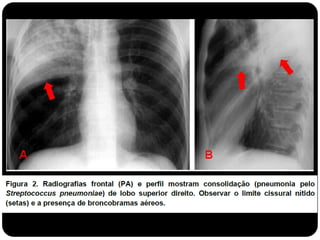

Atelectasia do LoboSup. D. (compare com slide anterior que era consolidação de LSD!)

Conceitos  Atelectasia: ausênciado ar alveolar;  Consolidação: substituição do ar alveolar (não há redução de volume);

• 32.

 Quando ocorreessa consolidação os brônquios em seu interior podem tornar-se visíveis – broncograma aéreo.